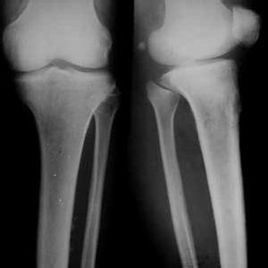

非骨化性纖維瘤有典型的X線特徵,病變始於長骨的乾骺端,靠近骺板,且總在一側皮質上膨脹、偏心性隨骨的生長發育病變可以逐漸向骨幹移行,病灶內為界限清楚透亮陰影,呈分葉狀卵圓形,周邊有一硬化緣。病變縱軸與長骨一致,病變小自1cm,最大可達15cm。病變發展有侵入髓腔、破壞整個乾骺端導致整個皮質變薄,造成病理性骨折。病變可隨骺板生長而擴大,骺閉合後病變有可能停止生長。

多發非骨化性纖維瘤影像學也有典型特徵性表現,可在同一骨內有多個病灶,也可不在同一骨。